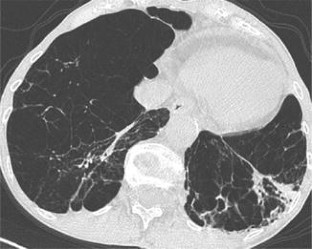

Alpha-1 antitrypsin deficiency (AATD) is an inherited disorder characterized by low serum levels of alpha-1 antitrypsin (AAT). Loss of AAT disrupts the protease–antiprotease balance in the lungs, allowing proteases, specifically neutrophil elastase, to act uninhibited and destroy lung matrix and alveolar structures. Destruction of these lung structures classically leads to an increased risk of developing emphysema and chronic obstructive pulmonary disease (COPD), especially in individuals with a smoking history. It is estimated that 3.4 million people worldwide have AATD. However, AATD is considered to be significantly underdiagnosed and underrecognized by clinicians. Contributing factors to the diagnostic delay of approximately 5.6 years are: inadequate awareness by healthcare providers, failure to implement recommendations from the American Thoracic Society/European Respiratory Society, and the belief that AATD testing is not warranted. Diagnosis can be attained using qualitative or quantitative laboratory testing. The only FDA approved treatment for AATD is augmentation therapy, although classically symptoms have been treated similarly to those of COPD. Future goals of AATD treatment are to use gene therapy using vector systems to produce therapeutic levels of AAT in the lungs without causing a systemic inflammatory response.

Sverzellati N, Molinari F, Pirronti T, Bonomo L, Spagnolo P, Zompatori M (2007) New insights on COPD imaging via CT and MRI. Int J Chronic Obstruct Pulm Dis 2(3):301–312

Yuan R, Nagao T, Paré PD, Hogg JC, Sin DD, Elliott MW, Loy L, Xing L, Kalloger SE, English JC, Mayo JR, Coxson HO (2010) Quantification of lung surface area using computed tomography. Respir Res 11(1):153